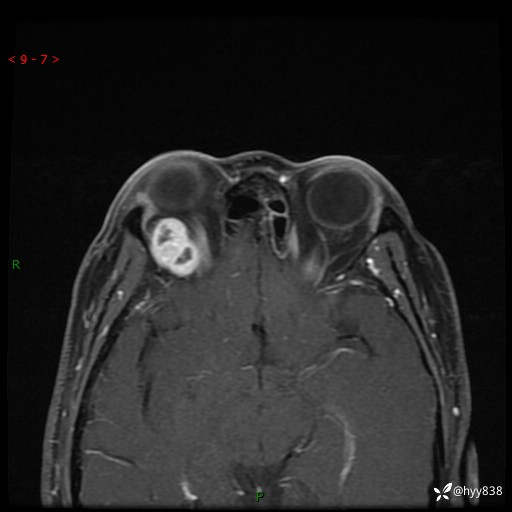

老年女性,右眼球突出1月。说说鉴别诊断,看谁第一个秒---(有结果)

主诉:发现右眼球突出1月余

简要病史:患者于1月前无明显诱因发现右眼球突出,偶感磨痛、眼胀,无视力下降,无头痛,恶心呕吐等不适。10天前就诊于当地县人民医院就诊,完善头颅ct检查,诊断为右侧眼眶肿物,建议患者上级医院进一步治疗,患者因个人原因拒绝。拟行手术,来我院就诊,门诊行相关检查后以“右眼眼眶肿物”收入院。 患病以来,患者精神饮食睡眠尚可,大小便如常、体重无明显改变。

辅助检查:MRI

临床诊断:眼眶肿物

眼眶MRI平扫+增强